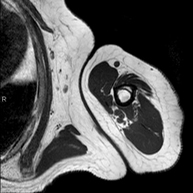

Prova diagnòstica no invasiva que consisteix en l'obtenció d'imatges d'alta definició anatòmica de la regió escrotal mitjançant l'ús d'un camp electromagnètic i ones de ràdio (amb un emissor i un receptor). No utilitza radiació ionitzant. De vegades s'ha d'emprar contrast paragmanètic (Gadolini) per completar l'estudi. S'utilitza per a l'estudi detallat dels testicles, per identificar possibles tumors i diverses patologies i per visualitzar alteracions de les estructures adjacents. - RM peniana